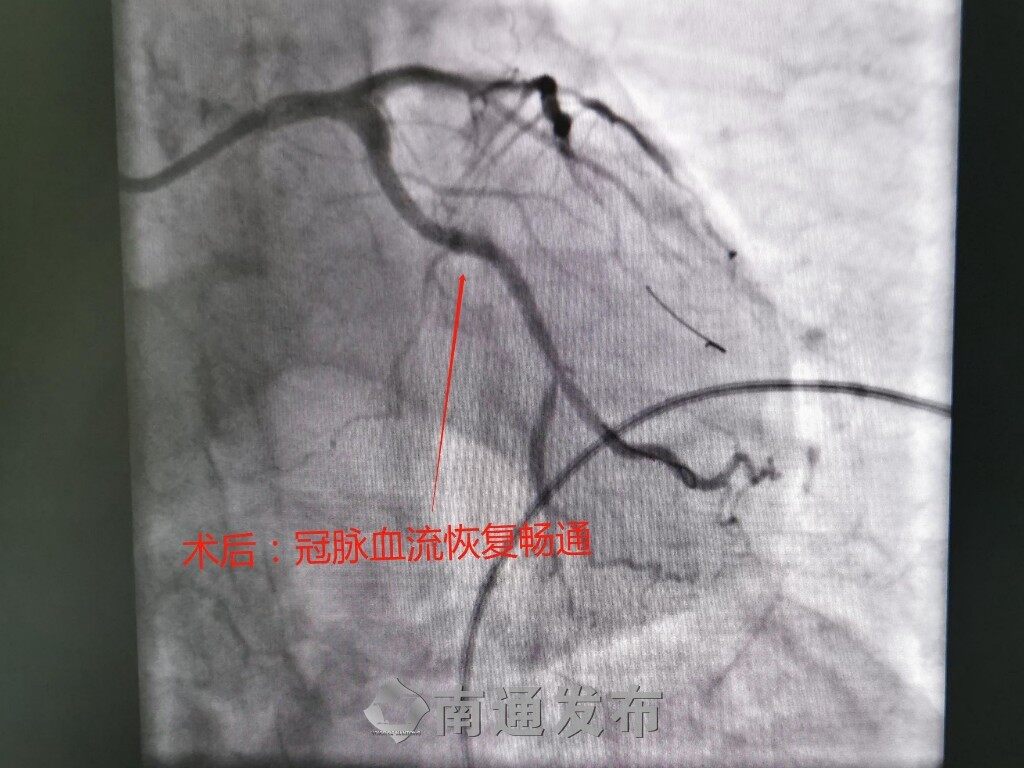

清除了血管内腔通道里的“拦路石”,冠状动脉支架得以顺利置入,冠脉血流恢复畅通。复查造影显示,支架扩张良好,无残余狭窄,手术成功。“之前一活动就感觉喘不上气,憋得难受,手术后感觉一下子舒服多了。”王老伯的胸闷气促等症状在术后明显改善,气色也恢复了不少。